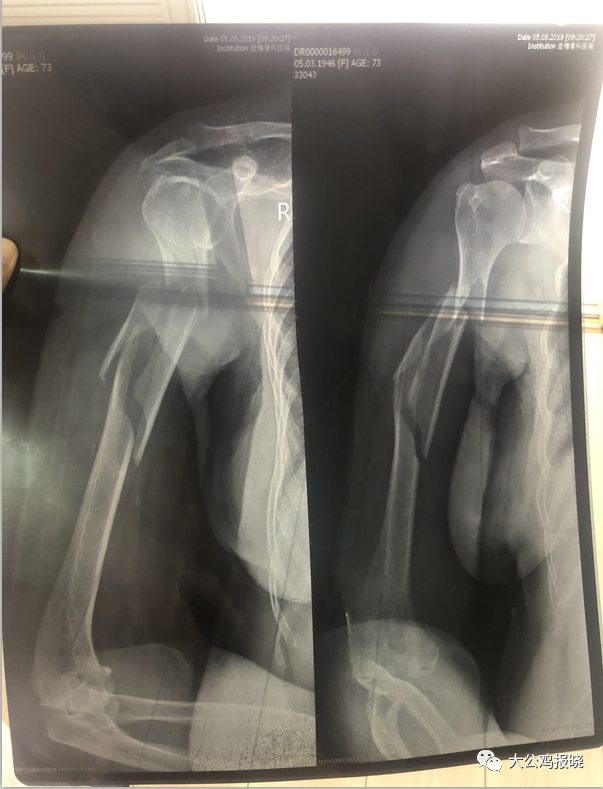

付老太太拿出一张肱骨骨折的老太的片子,和我们讲了事情经过。

阚#芳,女,73岁,盘锦市双台子区,2019年5月14日右侧肱骨骨折,去市中心医院拍片,告诉无法治疗,因为骨质疏松严重,无法手术打钢钉,简单打上石膏、让回家养。

听人介绍来访,求助中医治疗

CT显示:右侧肱骨干见多发骨质断裂影响,断端对位不良,周围软组织肿胀(呈紫色)右肱骨干粉碎性骨折。

治疗(第一次):剪开石膏,上肢肿胀严重,呈深紫色,触摸患处软组织僵硬,手法轻柔按抚、复位、端正骨折处明显手感骨擦音,复正几次后,小夹板加压捆扎。

(第二次):来时打开包扎,见明显消胀,肤色变浅,水洗法手法复正抚平,加压包扎固定。

(第三次):复正水洗,加压固定,连续三日要求隔日、隔2、3、5、7日逐渐时间拉长复诊。

7日后肿胀消退,肤色变黄,患处痒,7--15天为生长期,血形淤去骨才生。

二十日后患肢处肿胀全无,无棘痛感,无僵硬肤色,恢复正常,因年龄较大,骨质疏松严重,吃些自买药、营养用餐、心情疏畅、骨正筋柔、气血自流、现痊愈。